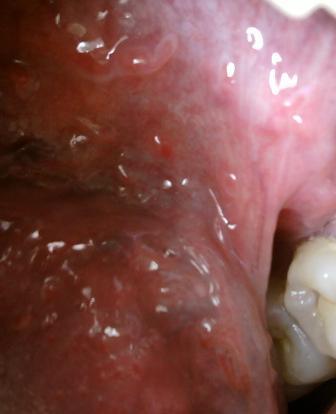

尖锐湿疣治好之后就不再复发了吗尖锐湿疣不仅是比较难治疗的,而且也是容易复发的。通常疾病之后的三个月的时间,是疾病复发的高峰期,建议大家在此时应该谨慎,多加注意,尖锐湿疣疾病是一种很复杂的疾病,这种疾病的出现会给很多病人带来严重的危害,所以请大家注意。